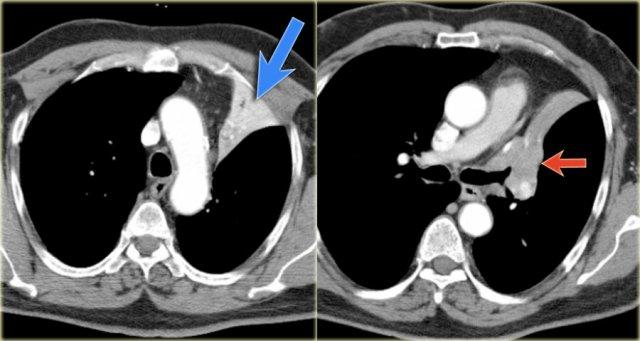

Xẹp thùy trên phổi trái

Hãy quan sát kỹ các hình X-quang trước, sau đó tiếp tục đọc.

Các dấu hiệu là gì?

- Mất thể tích tối thiểu kèm nâng cao cơ hoành trái

- Dải tăng tỷ trọng trong khoang sau xương ức, đây chính là thùy trên phổi trái bị xẹp

- Rốn phổi trái bất thường, gợi ý có thể có khối gây tắc nghẽn

- Các dấu hiệu này cho thấy xẹp thùy trên phổi trái

Các hình ảnh CT cho thấy xẹp thùy trên phổi trái (mũi tên xanh dương).

Có một khối ở vị trí trung tâm gây tắc nghẽn phế quản thùy trên phổi trái (mũi tên đỏ).